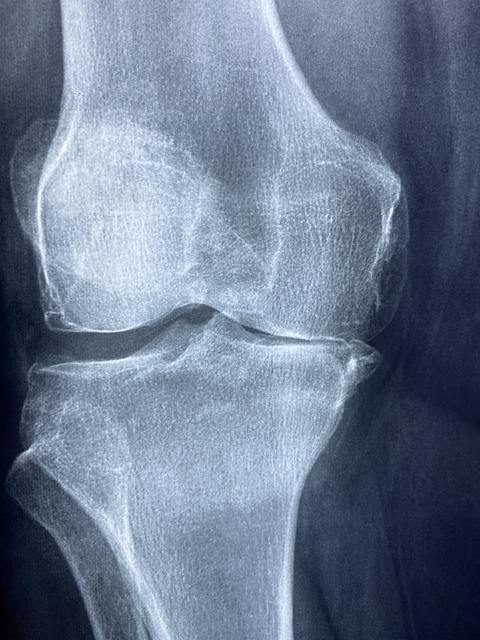

- X-레이: 슬개골과 대퇴골 사이의 정렬 상태를 평가하고, 뼈의 구조적 문제가 있는지 확인합니다. 그러나 X-레이는 연골 자체는 보여주지 않습니다.